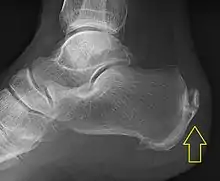

.jpg.webp)

Achilles tendinitis is usually diagnosed from a medical history, and physical examination of the tendon. Projectional radiography shows calcification deposits within the tendon at its calcaneal insertion in approximately 60 percent of cases.[17] Magnetic resonance imaging (MRI) can determine the extent of tendon degeneration, and may show differential diagnoses such as bursitis.[17]